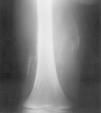

Con la impresión diagnóstica de dermatomiositis juvenil se repitieron los exámenes complementarios previos con resultados similares. Los autoanticuerpos fueron negativos. El antígeno de histocompatibilidad (HLA) del paciente era A2, A32, B37, B44, CW5, CW7, BW4, DR11, DR13, DQ6, DQ7, DR52. La radiografía de extremidades inferiores mostró calcificaciones en el muslo derecho (fig. 1) y zonas de aumento de densidad de partes blandas no calcificadas en muslo izquierdo. La resonancia magnética (RM) puso de manifiesto alteración bilateral periférica de la señal en varios grupos musculares; en el lado derecho la afectación era más significativa a nivel proximal del semimembranoso y semitendinoso, con alteración difusa de la señal en su inserción proximal en la tuberosidad isquiática, lo que sugiere desinserción parcial; en el lado izquierdo la afectación era menos marcada y más distal y afectaba a los músculos grácil y sartorio y con menor intensidad a los aductores; también existía afectación de la inserción distal del músculo recto femoral (fig. 2). El electromiograma fue normal. Las exploraciones cardiológica y oftalmológica fueron normales. La biopsia confirmó el diagnóstico de dermatomiositis juvenil y se inició tratamiento con deflazacort (2 mg/kg/día), añadiéndose a los 2 meses metotrexato semanal (10 mg/m2 por vía subcutánea). La dificultad para la deambulación y la tumefacción mejoraron progresivamente, aunque no llegaron a desaparecer.

Figura 1. Radiografía muslo derecho: calcinosis.